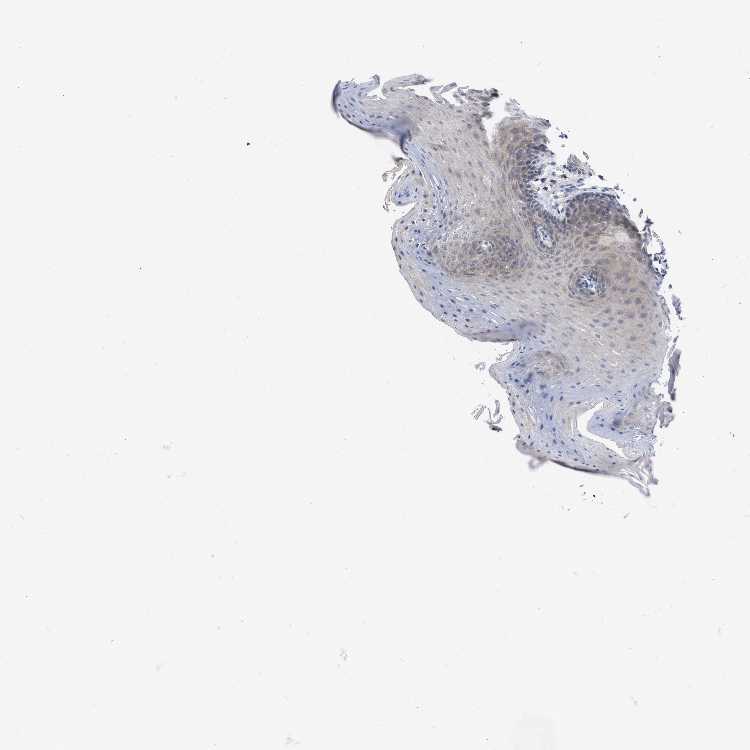

TISSUE PRIMARY DATA ORAL MUCOSA Show tissue menu

ORAL MUCOSA - Antibody stainingi

Antibody staining in the annotated cell types in the current human tissue is reported as not detected, low, medium, or high, based on conventional immunohistochemistry profiling in selected tissues. This score is based on the combination of the staining intensity and fraction of stained cells.

Each image is clickable and will lead to virtual microscopy that enables deeper exploration of all samples and also displays staining intensity scores, fraction scores and subcellular localization as well as patient and tissue information for each sample.

Antibody CAB022300

Squamous epithelial cells Medium